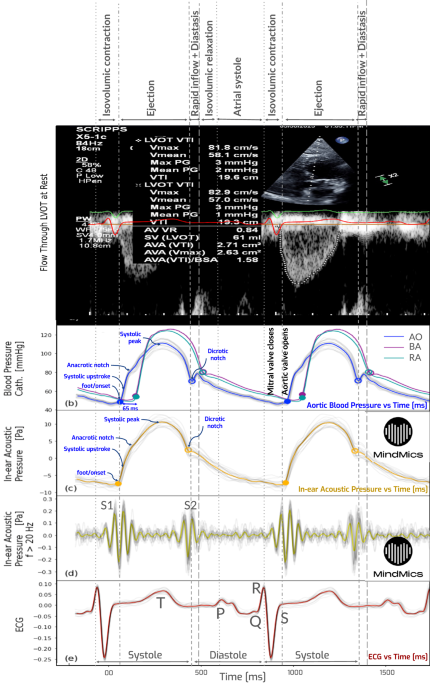

To evaluate the temporal relationships between cardiac events across multiple modalities, we generated a comprehensive set of Wiggers diagrams for study participants who underwent CC and had complete multimodal datasets comprising IH, 12-lead electrocardiography (ECG), echocardiography, and invasive aortic pressure recordings.

IH, aortic pressure, and ECG Lead II were recorded concurrently during CC at a sampling rate of 1 kHz. When available, peripheral pressure waveforms from the brachial, radial, and femoral arteries were also collected as the catheter advanced from the wrist or groin to the aorta. Although these peripheral traces were not acquired simultaneously with central signals, they serve to illustrate the progression of waveform morphology along the arterial tree. Doppler echocardiography of LVOT was typically obtained prior to catheterization and served as a reference for cycle timing.

To enable consistent temporal comparisons across modalities, cardiac cycles in both catheterization and IH signals were rescaled to match the inter-beat intervals (IBIs) extracted from the echocardiographic ECG trace. The signals were then aligned in time so that the QRS complexes in both echocardiogram and catheterization/IH ECGs were synchronized. Each Wiggers diagram panel includes, from top to bottom: LVOT Doppler flow, aortic pressure, IH waveform (corrected for instrument response), high-frequency IH (>20 Hz) revealing S1 and S2 sounds, and ECG Lead II. For each subject, 15 consecutive cardiac cycles were typically stacked to compute average waveforms. In cases where fewer high-quality consecutive segments were available across all modalities—such as in CAD11 and CAD17—nine and eleven cycles, respectively, were used. Across all panels, variability around the averaged waveforms was primarily due to respiratory modulation of cardiac signals.